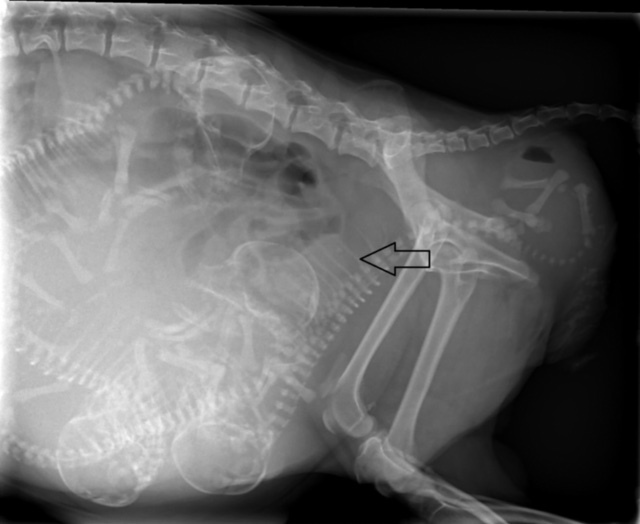

Letzteres ist gerade bei Chihuahuas mit ihren großen, runden Köpfen durchaus eine Möglichkeit, die einem in einem solchen Moment in den Sinn kommt. Wir entschieden uns, Bailey zu uns in die Praxis bringen zu lassen. Sie selbst war in guter Verfassung, ihre Wehen kamen kräftig in regelmäßigen Intervallen. Ein Röntgenbild brachte jedoch ans Licht, weswegen die Geburt nicht in die Gänge kommen wollte: Der erste Welpe befand sich in Hinter-Endlage auf dem Rücken liegend. An sich ist eine Geburt mit den Hinterbeinen voran beim Hund möglich, doch die Drehung des Fetus auf den Rücken verhinderte, dass sich sein Körper dem Geburtsweg seiner Mutter anpassen konnte. Er steckte fest. Von vaginal ließen sich seine Füßchen greifen und sein Körper in eine halbwegs aufgerichtete Position bringen – bei einer Mutter in der Größe eines Chihuahua kein leichtes Unterfangen – doch mit jeder Wehe drehte er sich wieder in die alte Lage zurück.

Als im Ultraschall die Herzfrequenz der übrigen Welpen sank, stand fest, dass ein Kaiserschnitt gemacht werden musste, um den Wurf und die Mutter zu retten. Das ganze Praxisteam versammelte sich im OP, um Baileys Babys auf die Welt zu helfen. Für den kleinen Unglücksvogel, der verkehrt herum geboren werden wollte, kam leider jede Hilfe zu spät. Er konnte nur noch tot geborgen werden. Die übrigen drei Welpen jedoch waren quietschlebendig entwickelt, trockengerubbelt und lagen wenige Minuten nach der OP bereits schmatzend am Gesäuge ihrer Mutter.